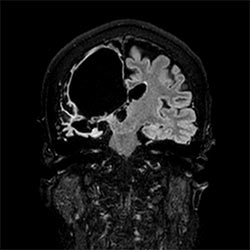

HeadNeck